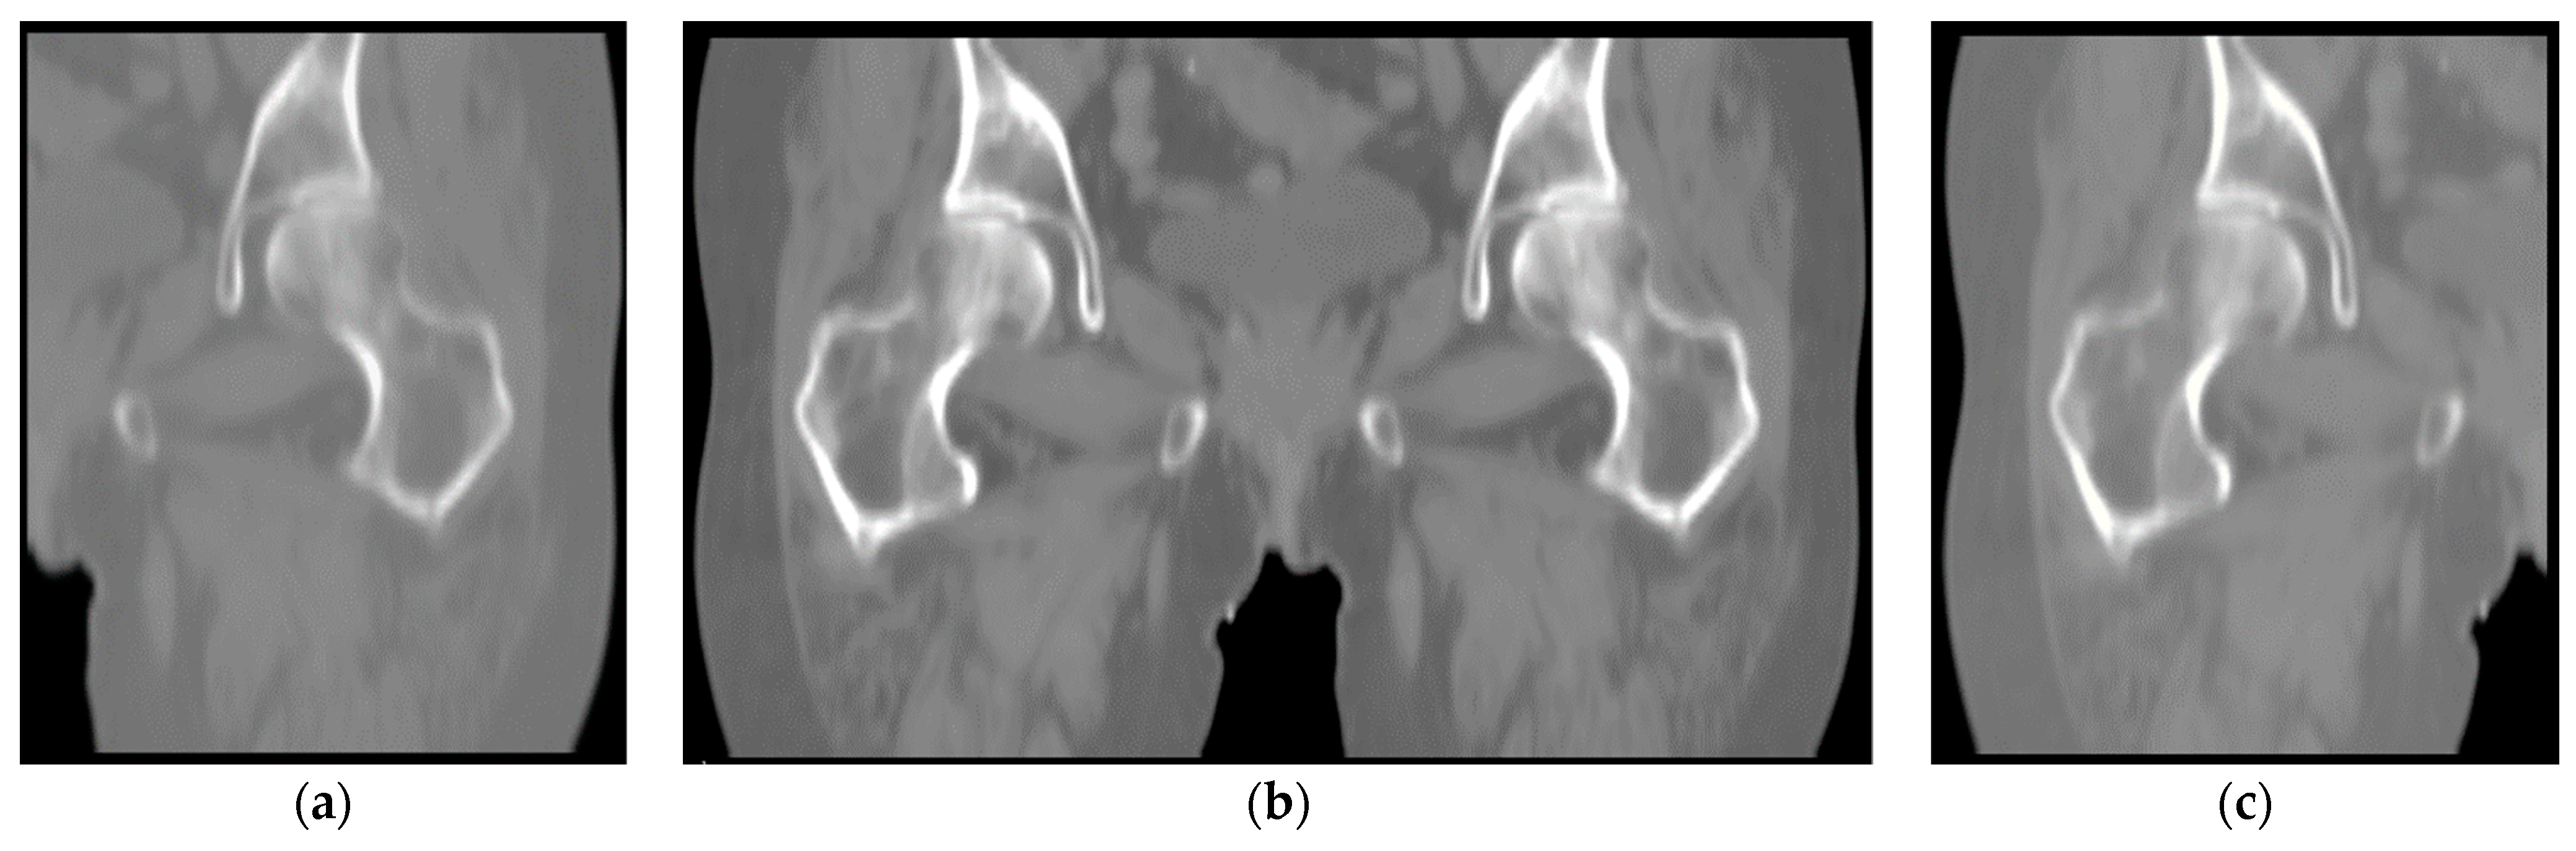

Figure 2 displays the coronal images viewed from the anterior side. The complete image (b) is shared between the two datasets, and as a complement, each of the two datasets also contains unique left femur (a) and right femur (c). In this way, we can simply expand the dataset and accurately distinguish between left and right femur when segmenting CT images that contain a complete structure. By removing the data with poor image quality, in Dataset A, we ended up with 112 images of the left femur, of which 84 images were used for training, and 28 images formed the validation set. Similarly, 113 images were collected in Dataset B. A total of 85 images were used for training, and 28 images were used for validation. Subsequently, manual annotation of the femur for the constructed dataset.

Figure 2.

Coronal images viewed from the anterior side: (a) left femur; (b) images shared by both datasets; (c) right femur.